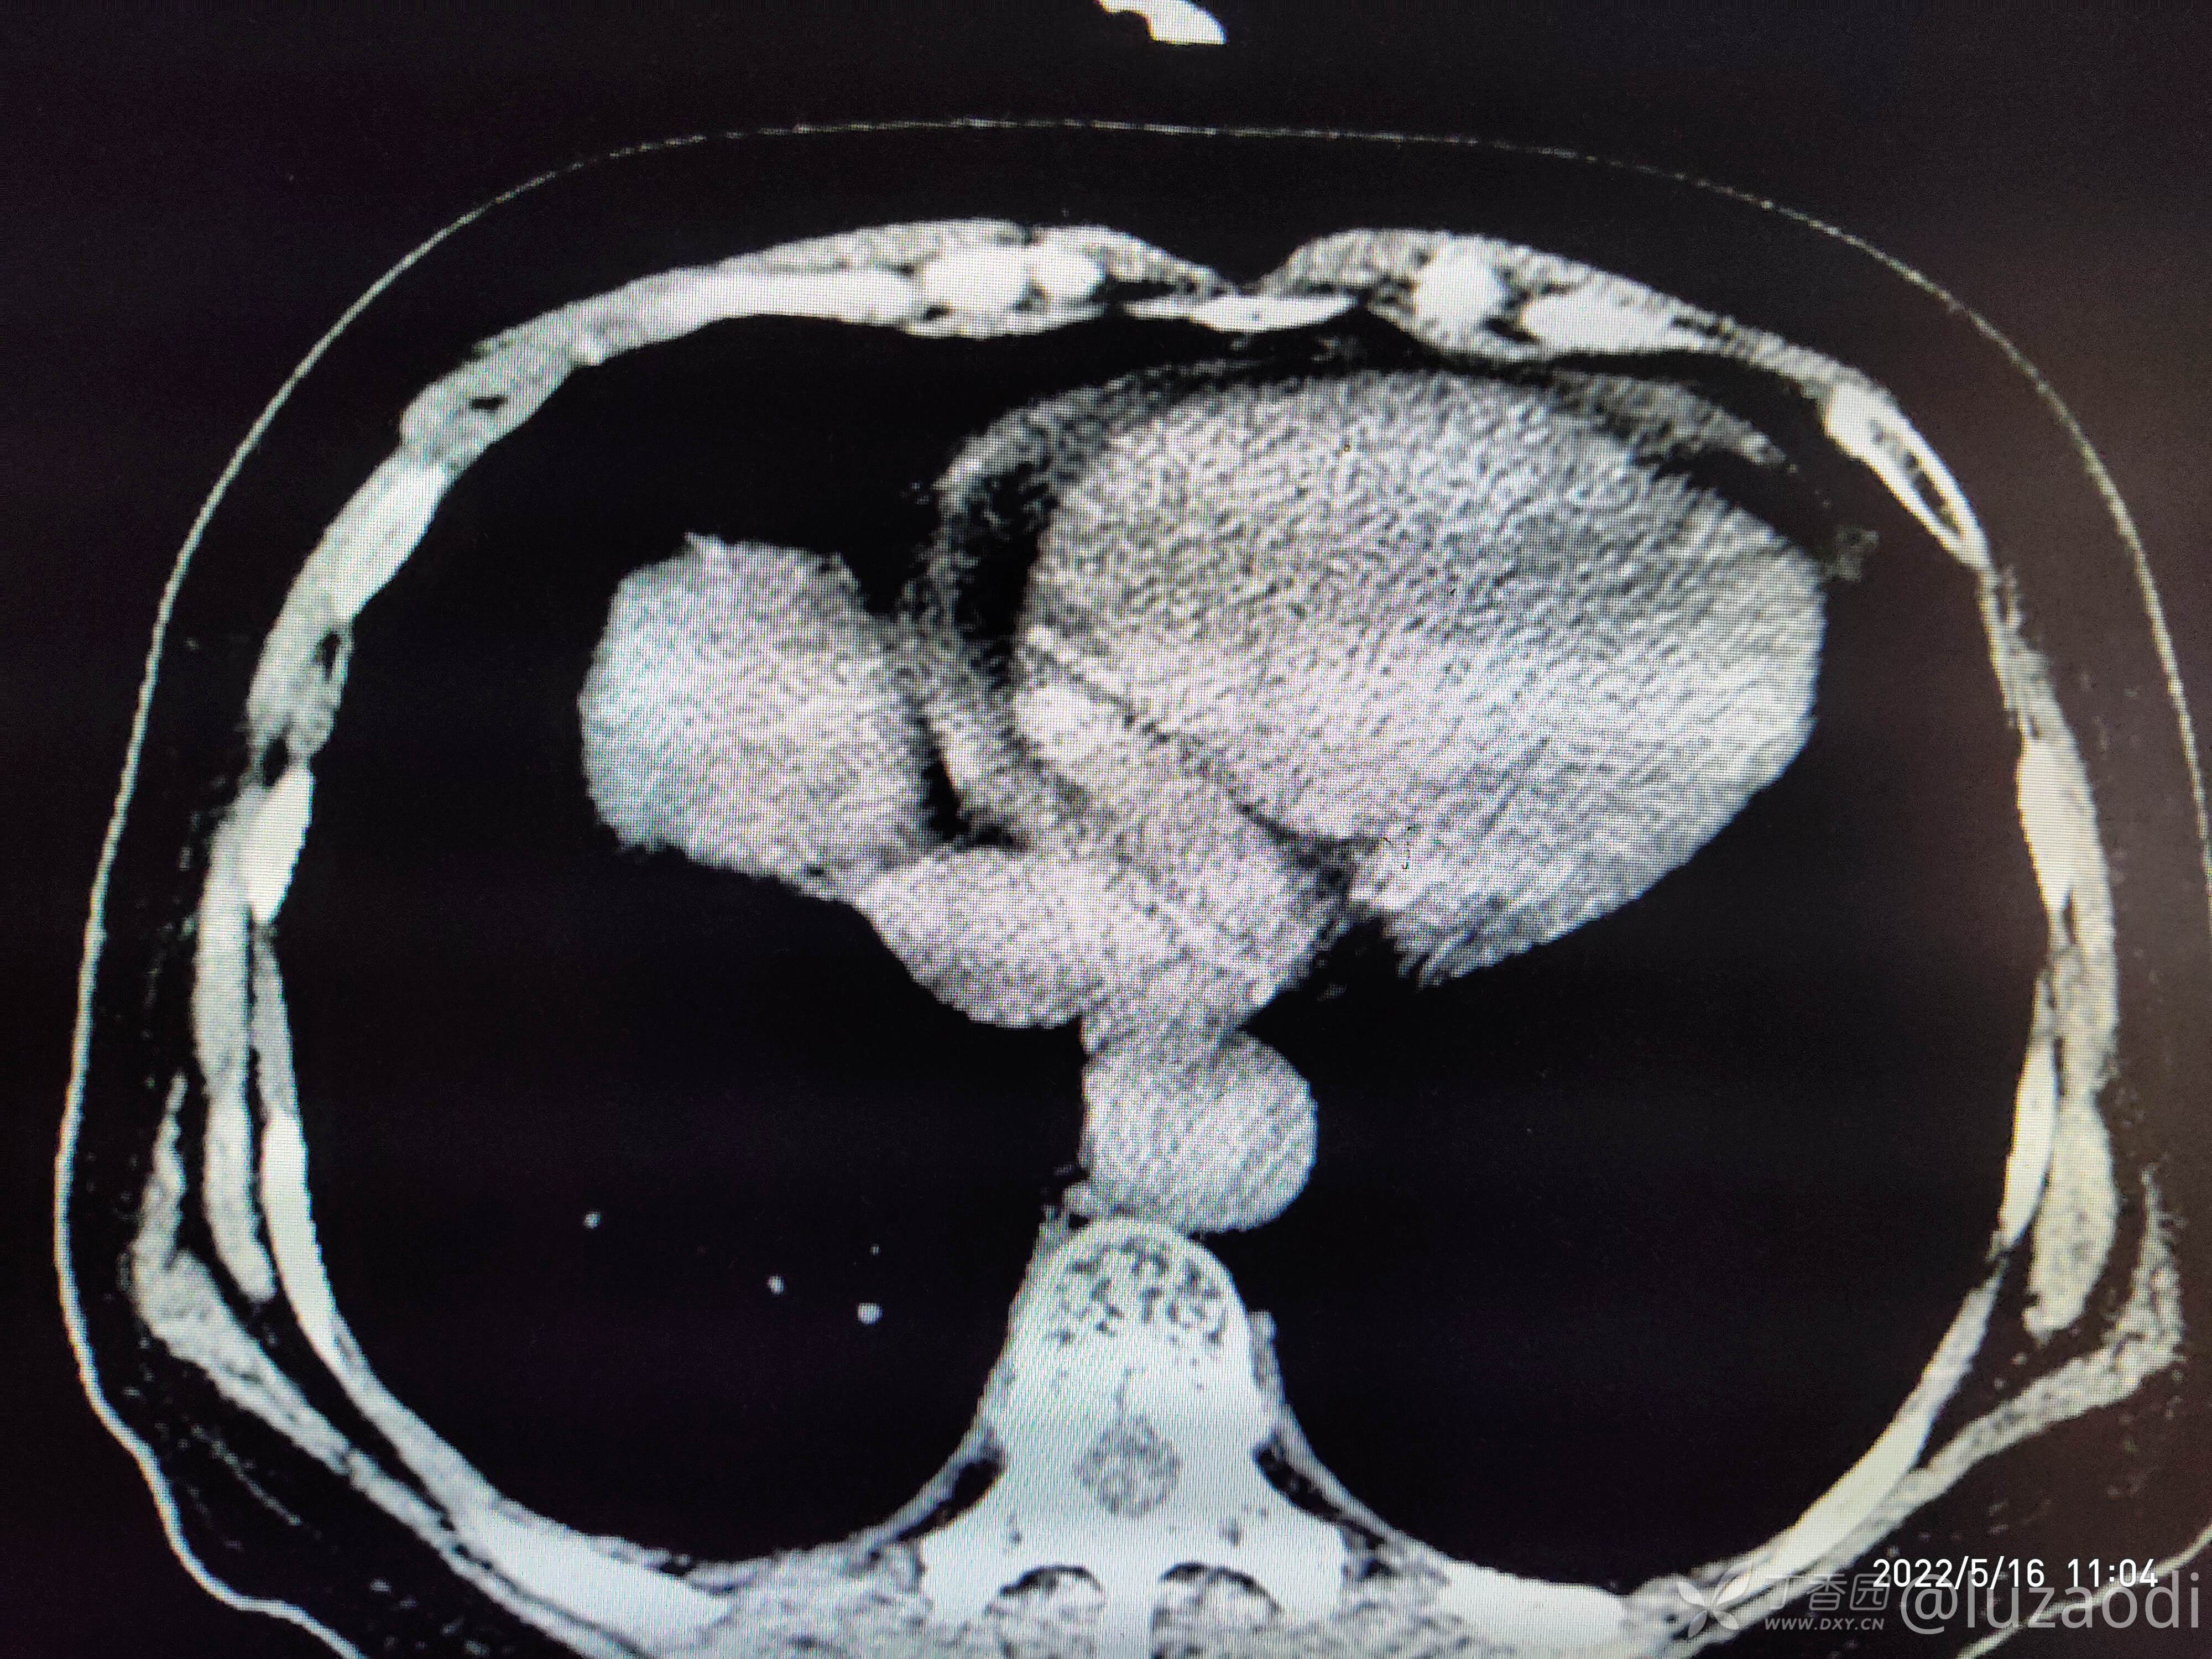

治疗经过:入院后患者仅有乏力,未见明显神经定位征。近期无发热、咳嗽、腹泻症状。遂予血糖、心电图、生化检查及影像检查,结果如下:

心电图将就着看,因为是手机拍的。

我去。。。。。视频只能上传一个,头颅CT上传不了,我直接说报告吧。头颅CT报腔隙性脑梗。